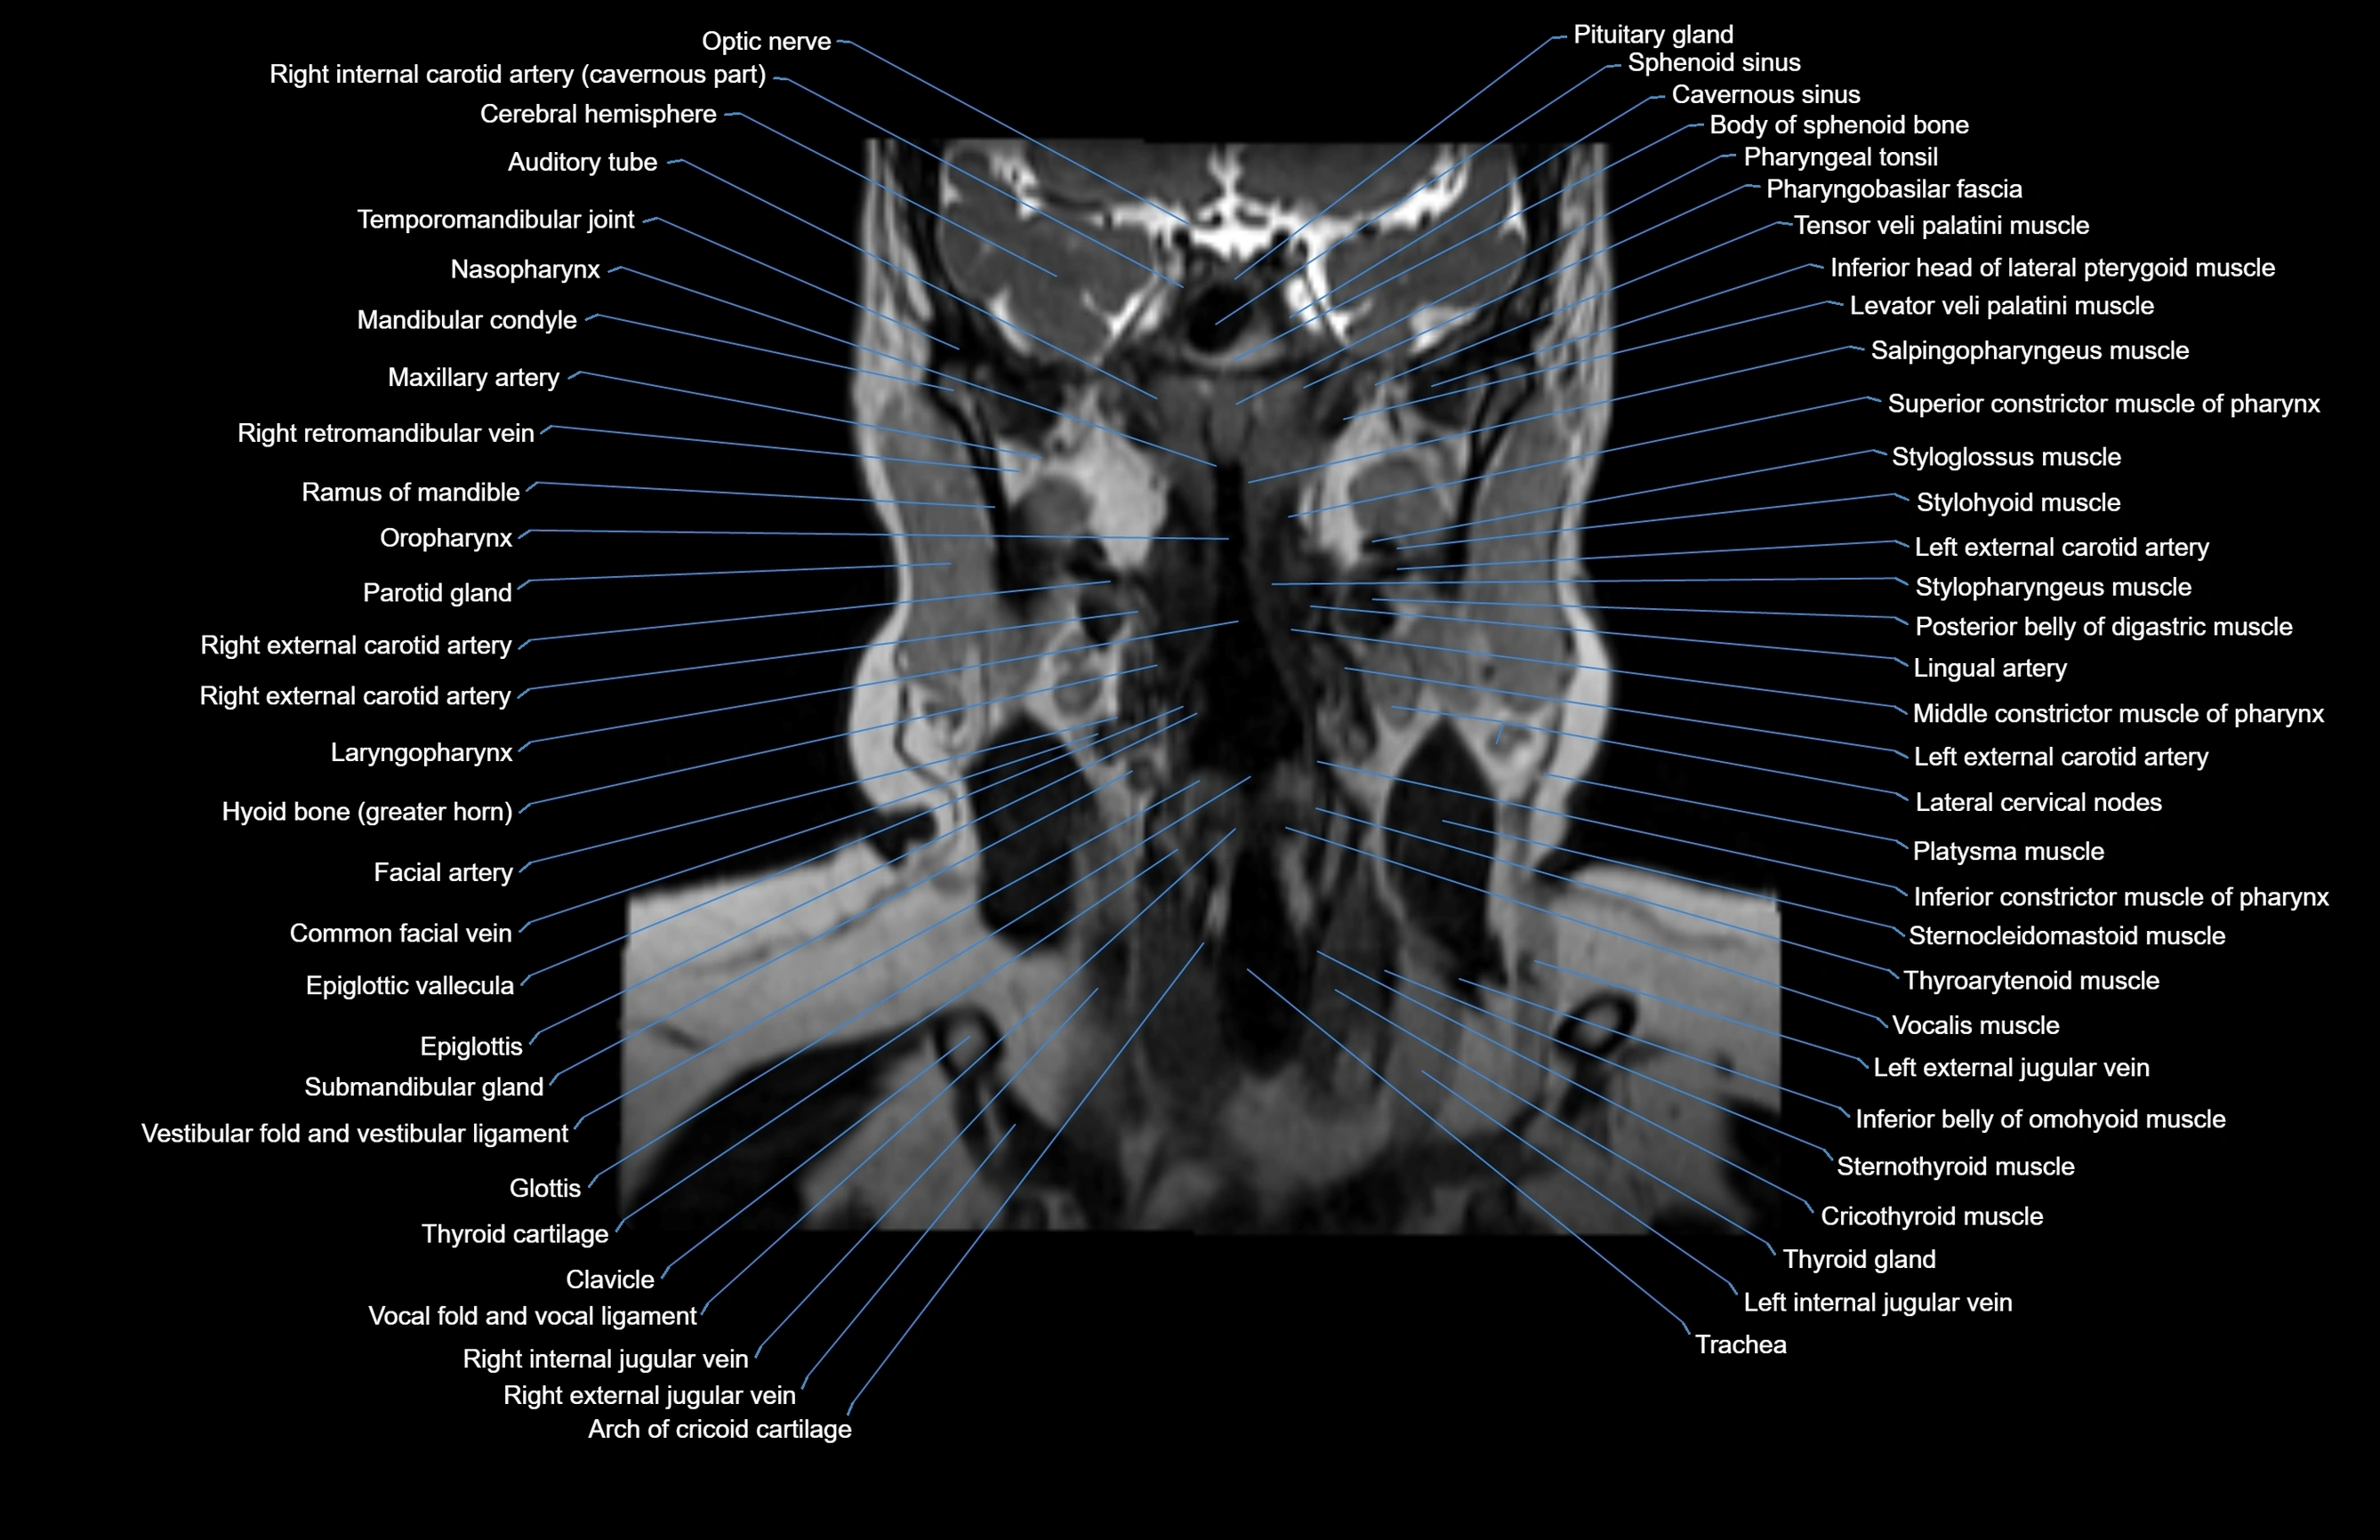

MRI images